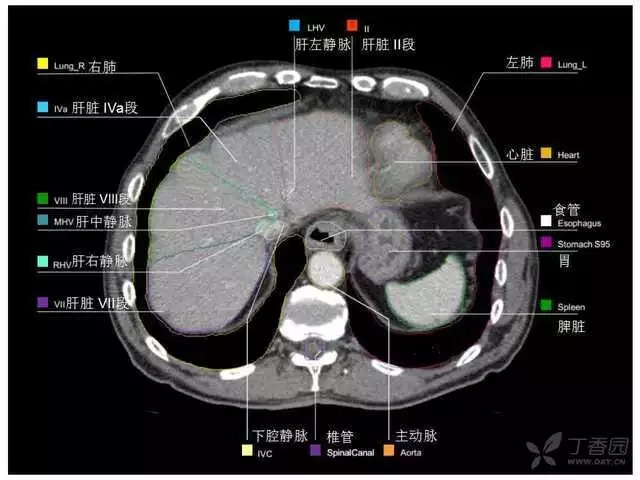

腹部肝脏高清CT断层的图谱

全腹部高清CT图谱,淋巴结彩色图谱,血管解剖图谱大汇总!

肝段,肝内管道的分布规律